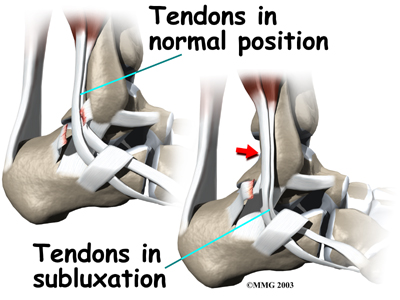

Tendons attach muscles to bone. Tightening a muscle puts tension on the tendon, which can move bone. Many tendons in the body are held in place by supportive connective tissue, such as a ligament or retinaculum. If the supportive tissue has been , the tendon may be free to slip out of its normal position. This is called . When the subluxed tendon slips back into place, this is called relocating. A tendon that forcefully snaps out of position and can't relocate has dislocated.

The main cause of peroneal tendon subluxation is an ankle sprain. A sprain that injures the ligaments on the outer edge of the ankle can also damage the peroneal tendons. During the typical inversion ankle sprain, the foot rolls in. The forceful stretch on the peroneals can rip the retinaculum that keeps the peroneal tendons positioned in the groove. As a result, the tendons can jump out of the groove. The tendons usually relocate by snapping back into place.

Patients describe a popping or snapping sensation on the outer edge of the ankle. The tendons may even be seen to slip out of place along the lower tip of the fibula. It is common to feel pain and tenderness . There may also be swelling just behind the bottom edge of the fibula.